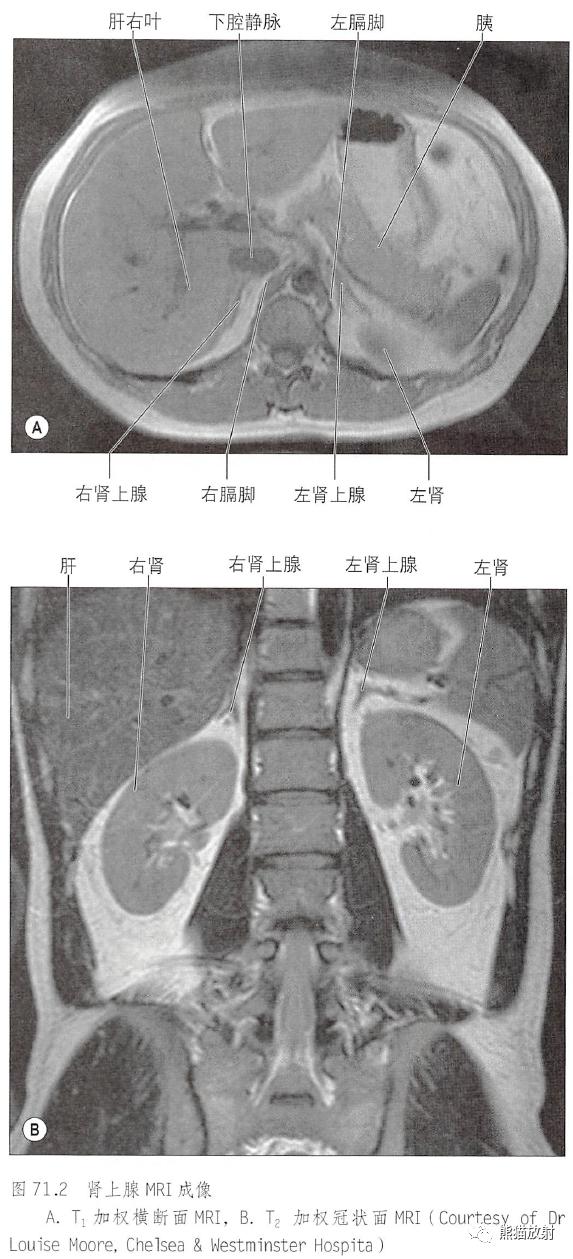

胰腺的毗邻肾上腺MRI:T1WI轴位、T2WI冠状位

肾上腺的动脉血供和静脉回流

肾上腺微观结构、主要功能